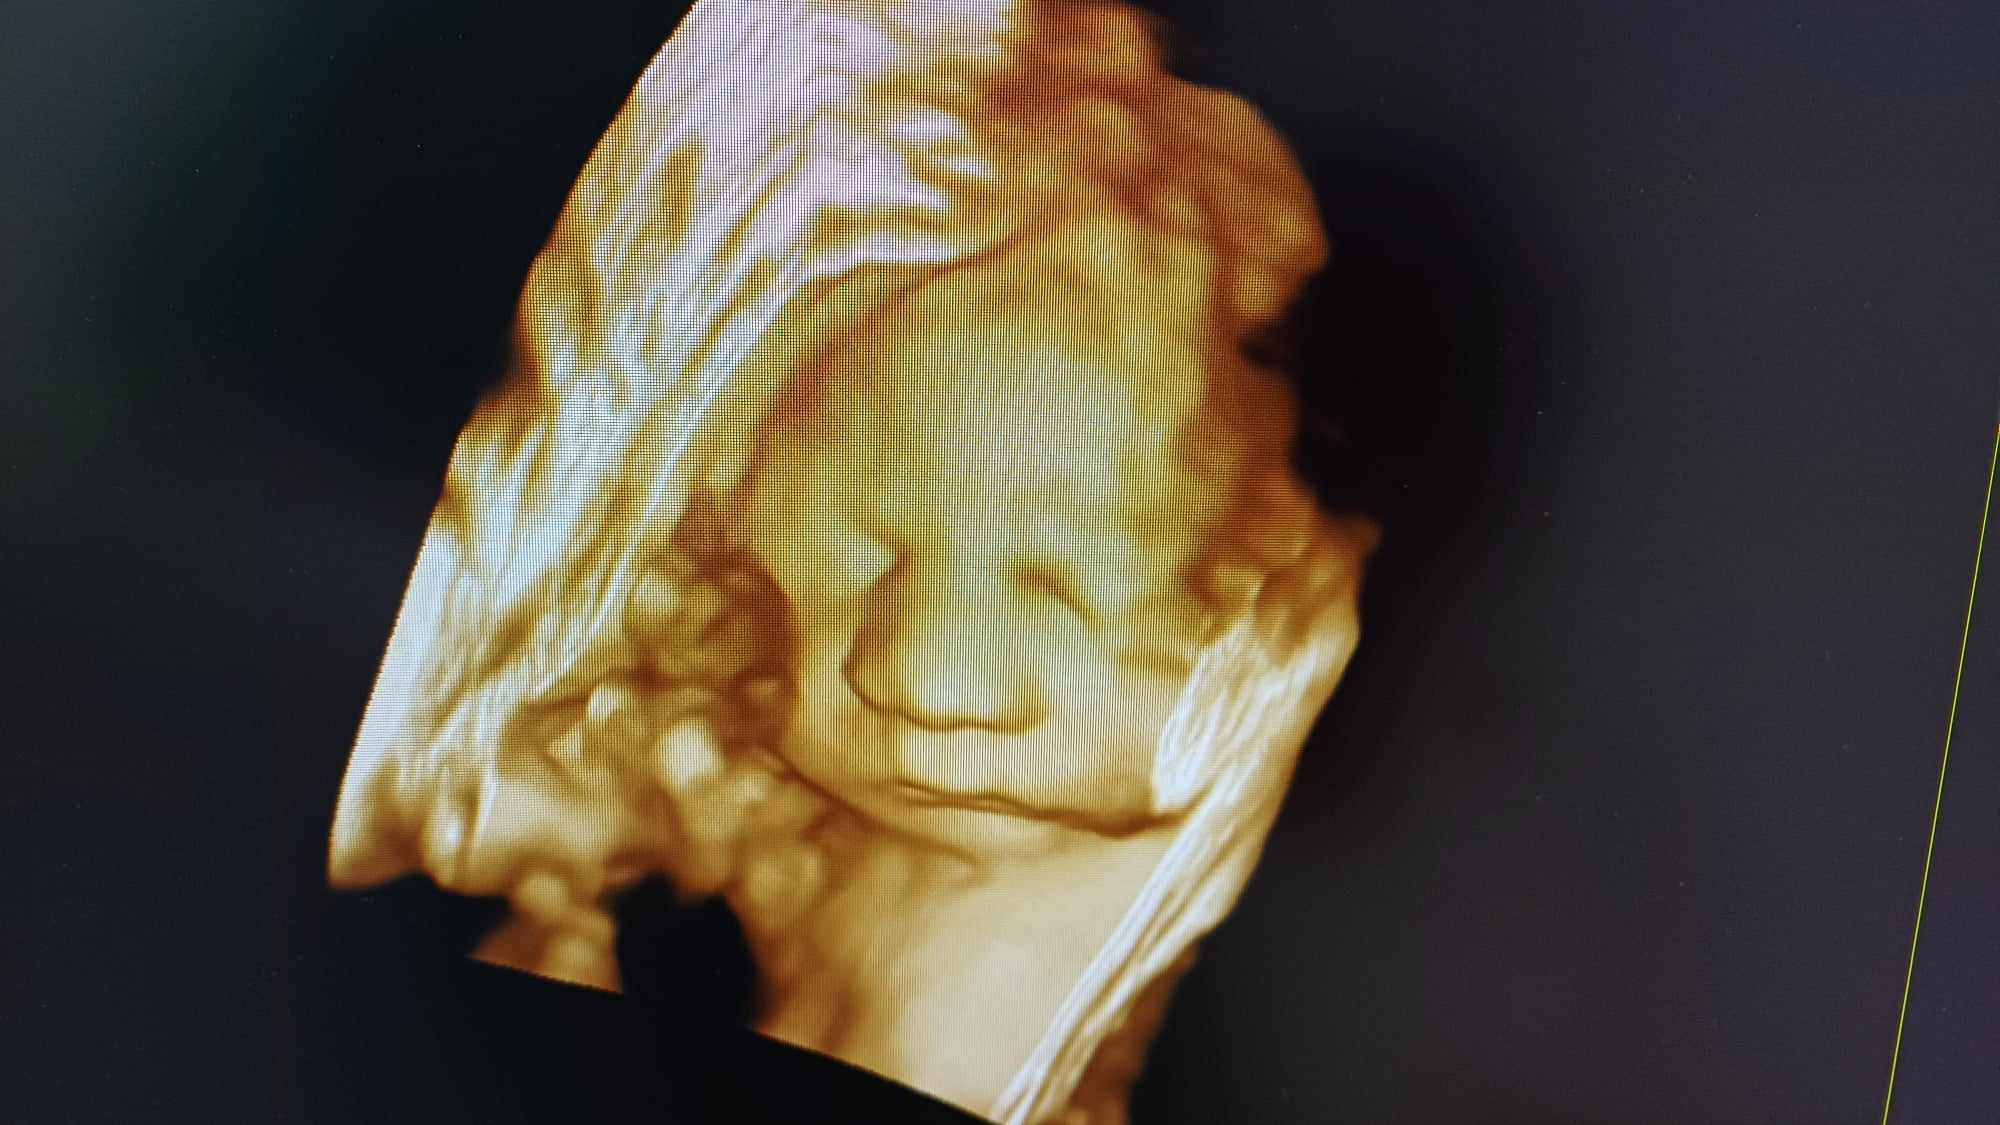

Pozrite si fotky z nášho moderného pracovného prostredia

Naša gynekologická ambulancia je vybavená modernou technikou a poskytuje pacientkom príjemné a komfortné prostredie pre všetky druhy vyšetrení a konzultácií.